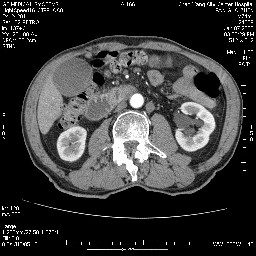

女,74岁,呕吐10余日

十二指肠水平段腔内占位伴梗阻,中等度较为均匀的强化,洗脱慢,区域淋巴结显示增多,符合腺癌表现。下腔静脉变异。

十二指肠降段扩张,水平段狭窄成鼠尾状,肠壁明显增厚,胰腺勾突增大成不均匀强化,其内可见低密度区,胆囊增大,1十二指肠水平段腺癌侵犯胰腺勾突可能大,2胰腺癌侵犯十二指肠(只有胆囊增大没有肝内外胆管扩张不好解释)代除外.

十二指肠降段扩张,水平段狭窄成鼠尾状,肠壁明显增厚,胰腺勾突增大成不均匀强化,其内可见低密度区,胆囊增大,1十二指肠水平段腺癌侵犯胰腺勾突可能大,2胰腺癌侵犯十二指肠 。

今日手术结果:胰腺钩突癌侵犯十二直肠,腹腔淋巴结转移.